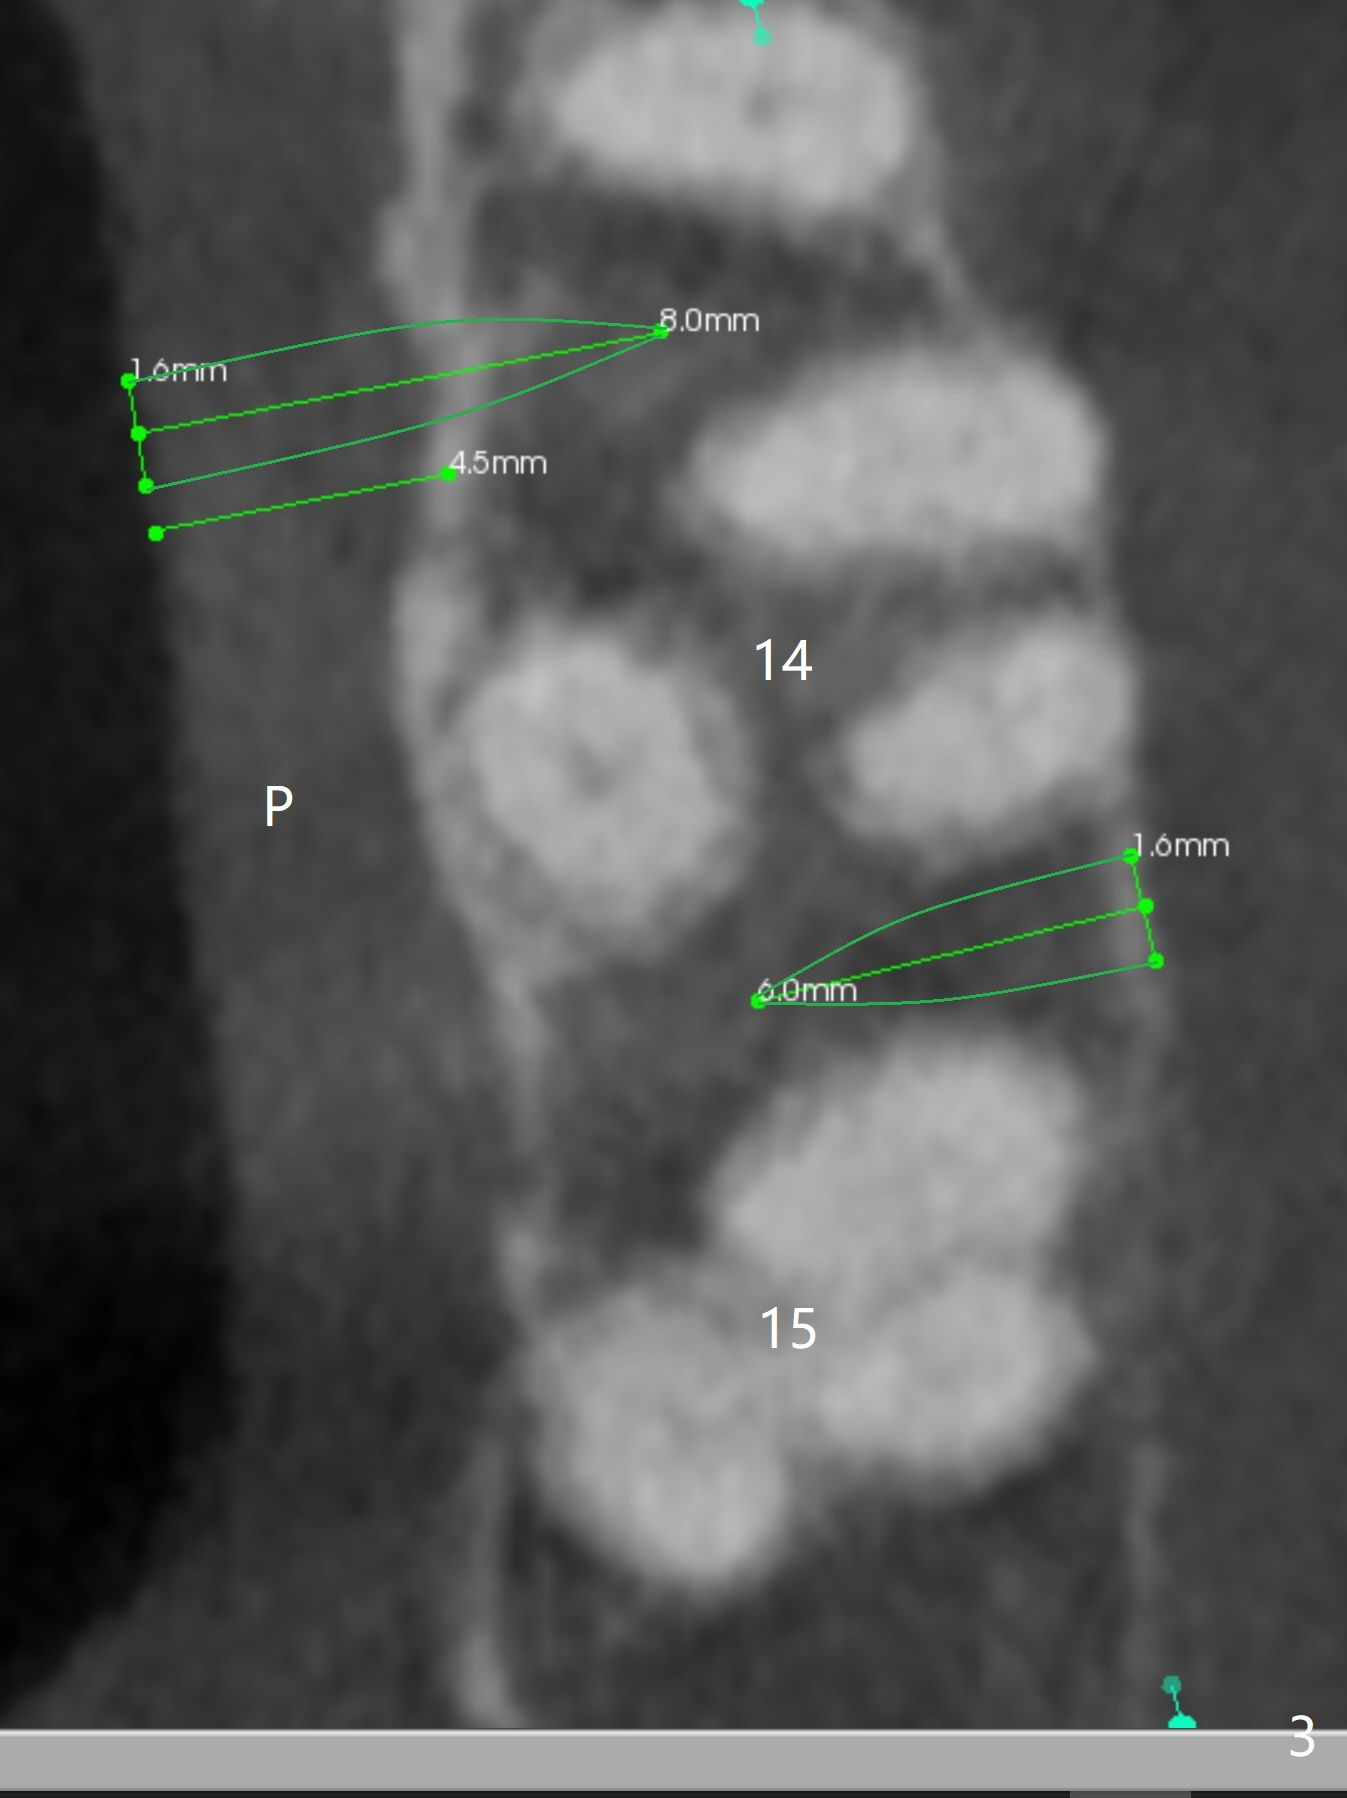

Two months post #19 implant placement, the patient will return to have #14,and 15 supraeruption (Fig.1 arrows) to be taken care of. It appears that there are suitable spaces for mini implants to be placed MP and DB relative to the tooth #14 (Fig.3). Since the palatal (P) mucosa is thicker, a longer mini-implant is expected (8 or 10 mm) palatally, vs. 6 or 8 mm buccally.